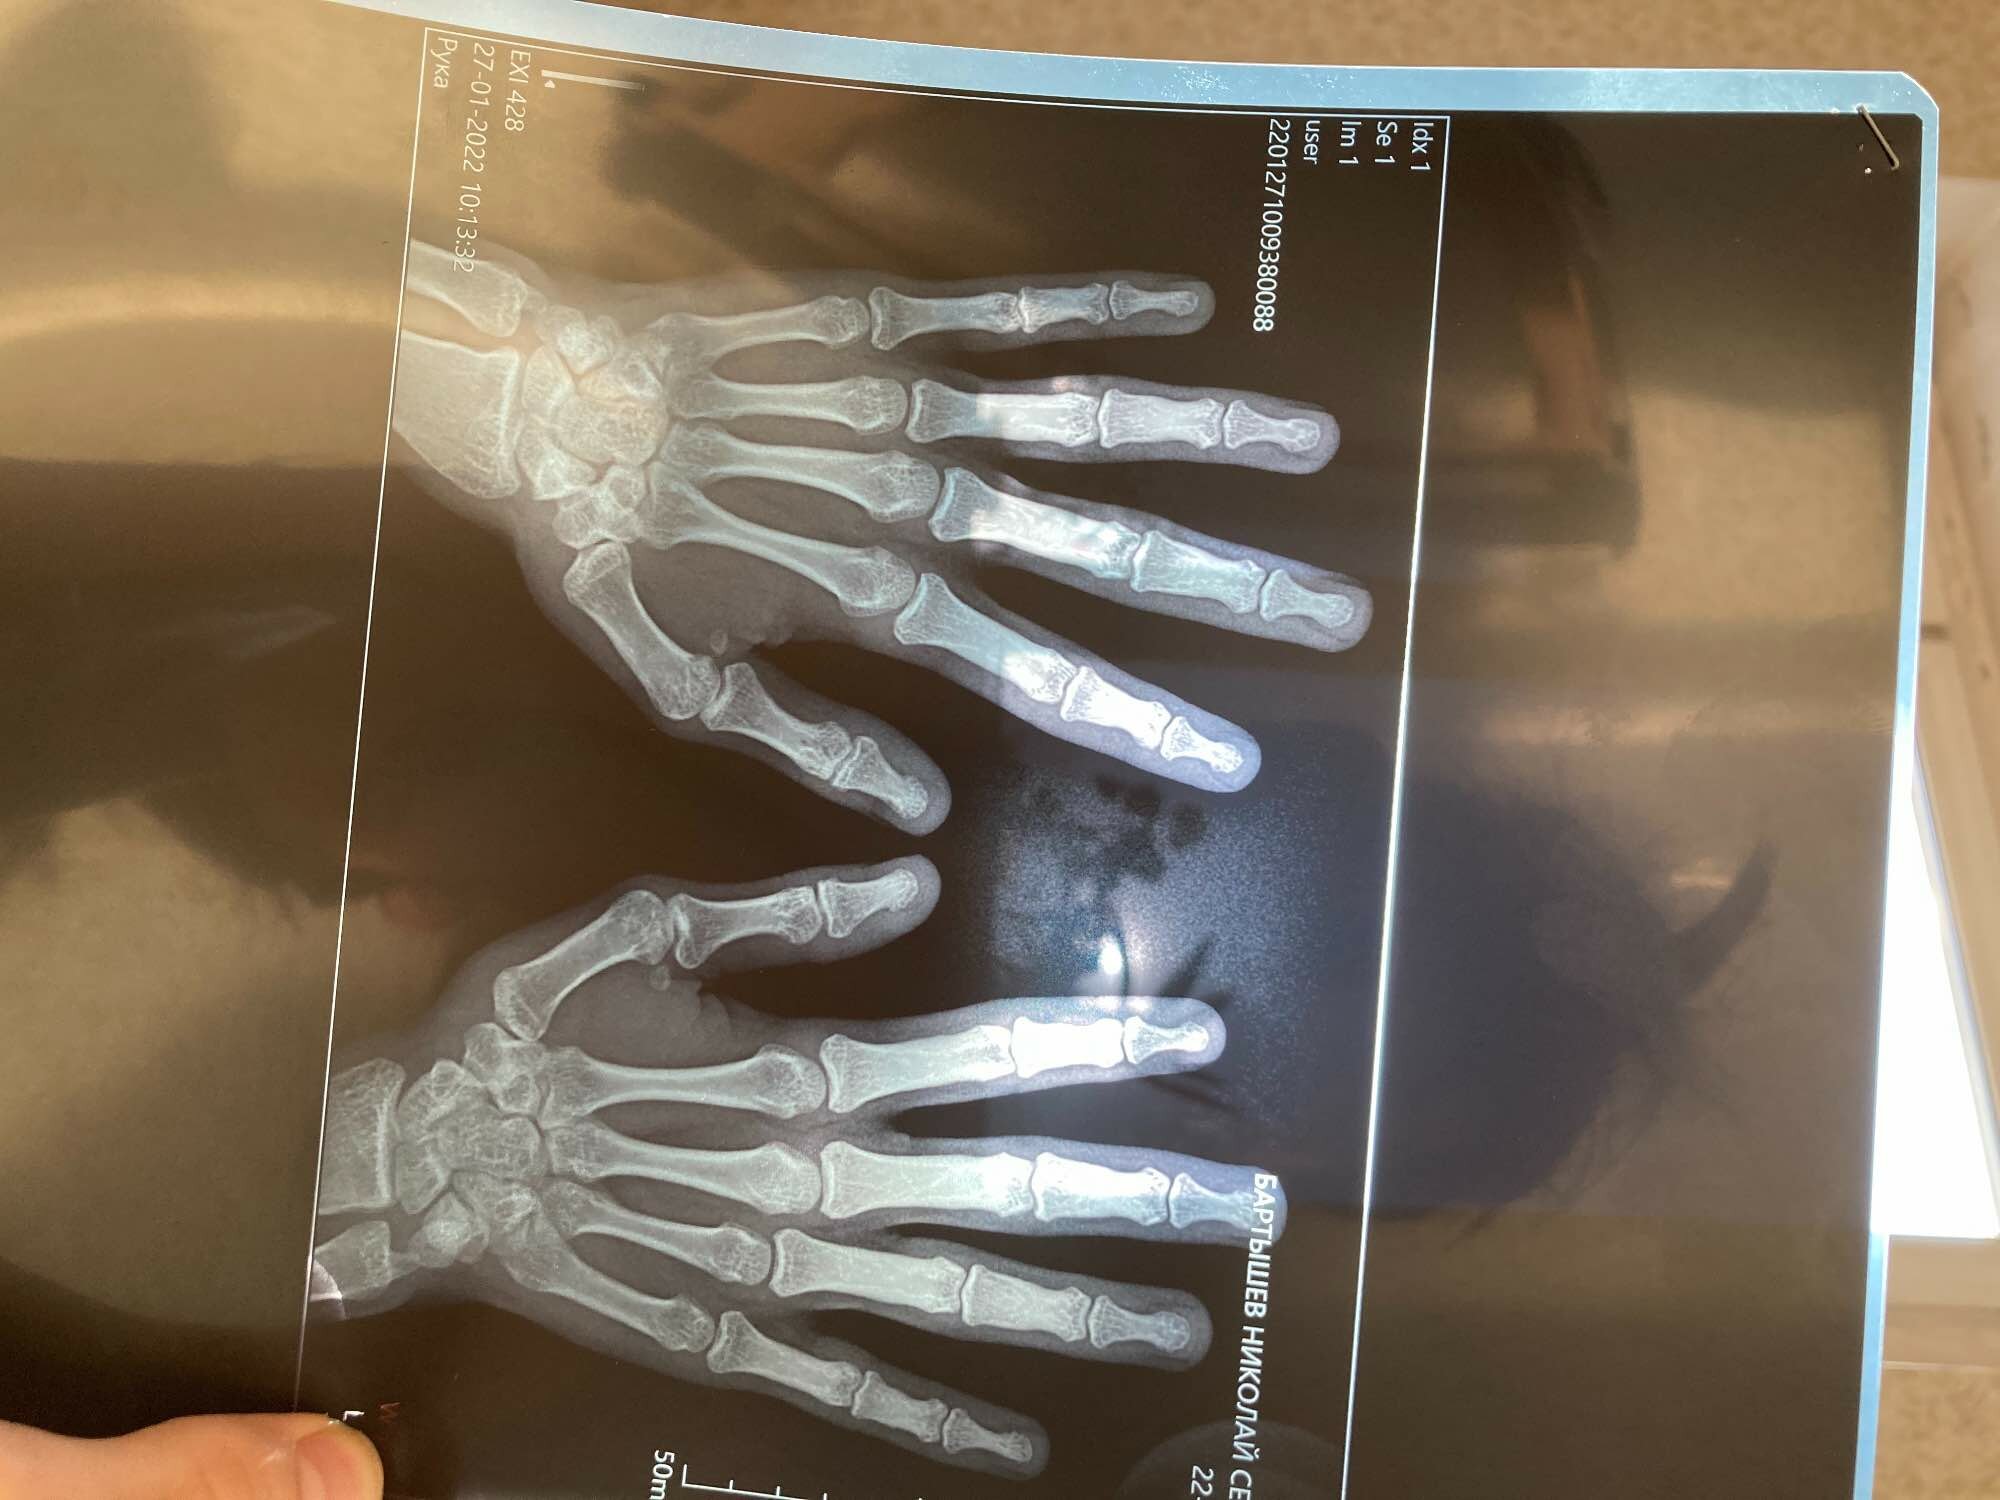

Хочу узнать на счет зон роста?Мне 20 лет. Прикрепляю рентген

Что же вы хотите узнать? Зон роста нет, уже закрылись